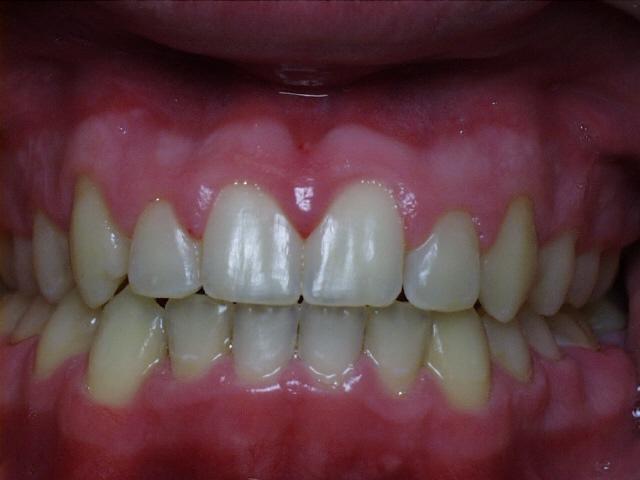

Severe overbite with mild upper and lower crowding.  Treatment time was 29 months.  No permanent teeth were extracted in this case.  The molars were class 2 (upper molars too far forward at start of treatment).  This patient can have bonding performed by his general dentist to repair the chipped front tooth.